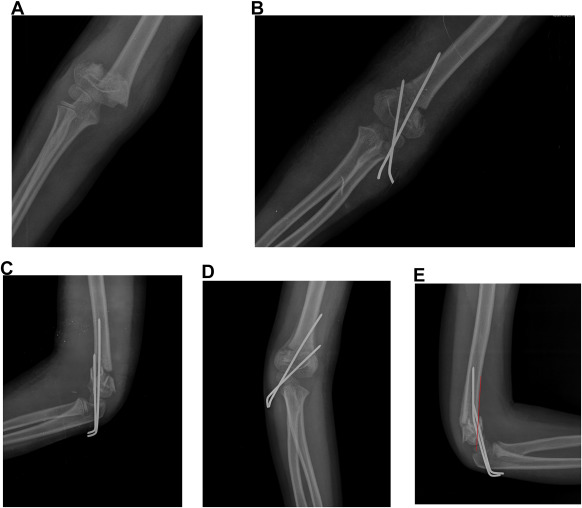

Direction of fracture displacement and fracture classification were assessed based on preoperative AP and lateral radiographs. Postoperative radiographic evaluation included true anterior-posterior radiograph and lateral radiograph of the elbow. Postoperative digital standard radiographs obtained after pin fixation at 3–4-week and 3-month follow-ups were postoperatively reviewed to determine LOR (Fig. 1 ).

Fig. 1. (A) Preoperative AP radiograph of type III supracondylar fracture. (B, C) Immediate postoperative AP and lateral radiographs revealing good reduction. Note medial wall comminution. (D, E) Radiographs taken at 4-week follow-up before pin removal showing reduction loss in coronal and sagittal planes. Red line indicates loss of reduction regarding the anterior humeral line. |